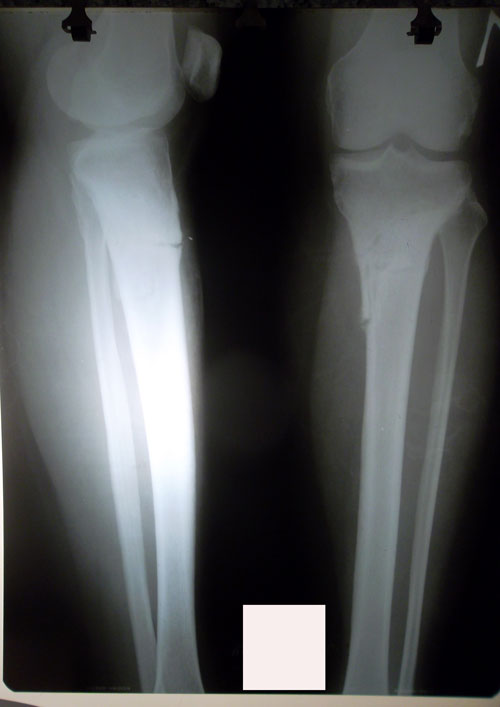

рентген в 20 дней с момента операции.

Сращение идёт отличное, как у 16 летней девочки!